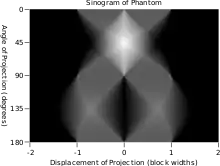

En el contexto de las tomografías la transformada de Radon se le suele llamar senograma puesto que la transformada de Radon de una función delta tiene como respuesta característica un seno. En consecuencia, la representación gráfica de la transformada de Radon de un conjunto de pequeños objetos parece una colección de senos con diferentes fases y amplitudes.

| Fantasma de Shepp-Logan; Transformada de Radon; y Transformada de Radon inversa | ||

lo que significa que la imagen original puede ser recuperada del 'sinograma' aplicando un filtro rampa (sobre la variable ) y entonces retroproyectando. Como que el paso de filtrado puede ser implementado de forma eficiente (mediante técnicas de procesamiento digital de señales) y la retroproyección no es más que una acumulación de valores en los píxeles de la imagen, resulta un algoritmo altamente eficiente, por lo que se trata de un algoritmo ampliamente usado.